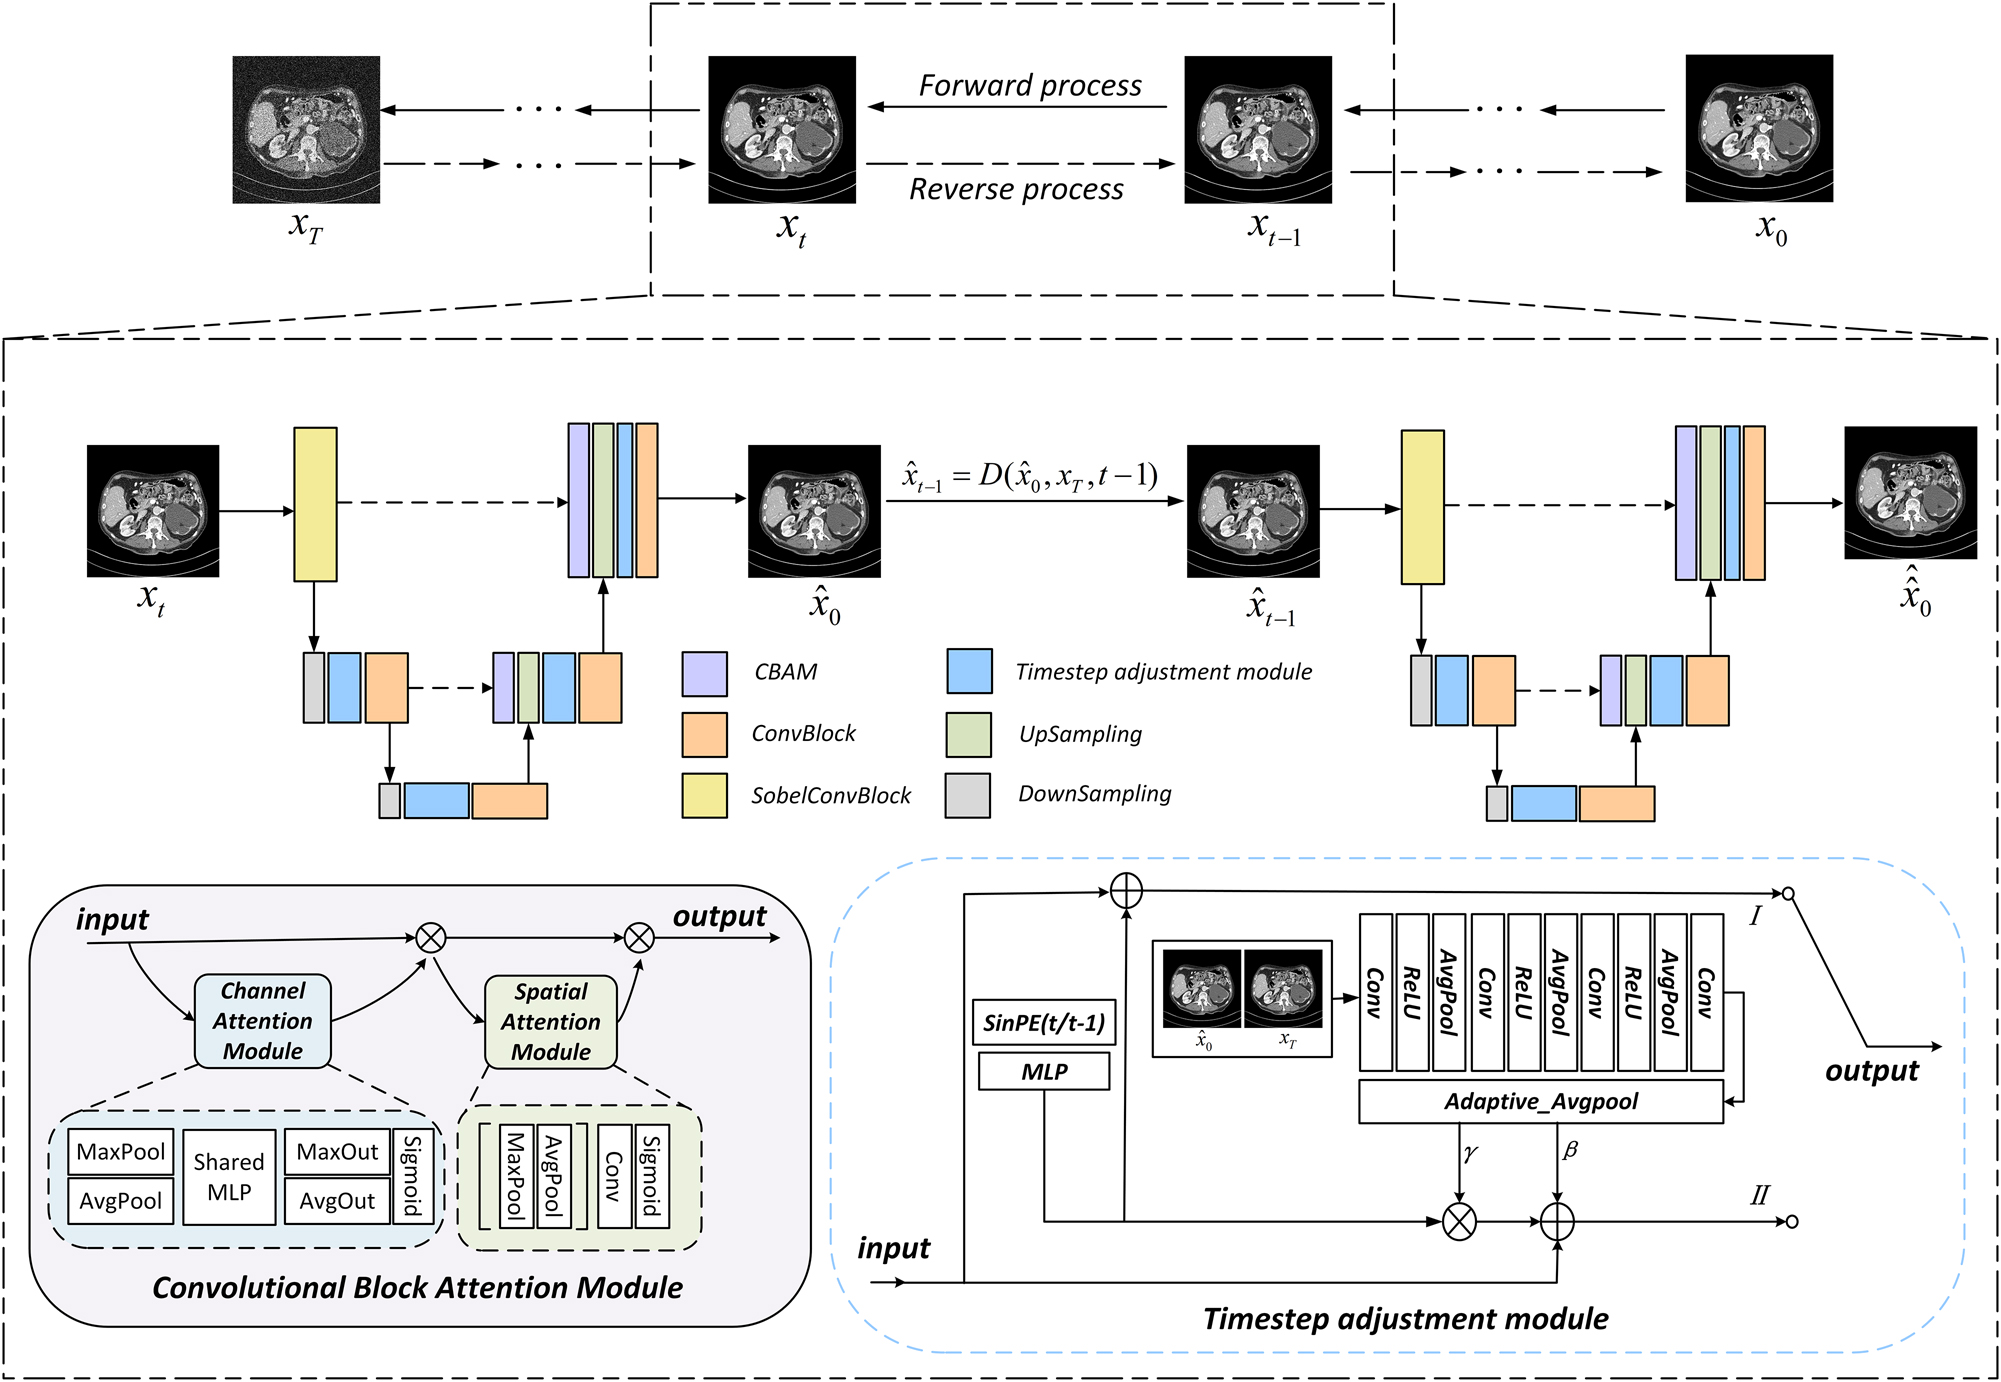

In recent years, the representation of diffusion models to produce high quality images and stable trainability has attracted wide attention. With the extension of the cold diffusion model to the classical diffusion model, its application has greater flexibility. Inspired by the cold diffusion model, we proposes a low dose CT image denoising method, called CECDM, based on the combination of edge enhancement and cold diffusion model. The LDCT image is taken as the end point (forward) of the diffusion process and the starting point (reverse) of the sampling process. Improved sobel operator and Convolution Block Attention Module are added to the network, and compound loss function is adopted.

Inspired by the cold diffusion model [26], we propose a low dose CT image denoising method, called CECDM, based on the combination of edge enhancement and cold diffusion model. NDCT image is taken as the starting point of the diffusion process, LDCT image is taken as the diffusion end point, and edge enhancement is further optimized on the basis of the network architecture proposed in CoreDiff. While ensuring the application speed of diffusion model, focusing on the performance of LDCT image denoising makes the image have better denoising effect while retaining more texture details.

Improved sobel operator and CBAM convolutional attention module are added to the network framework of the recovery network, which enables the model to extract edge information more accurately, overcome the smoothing problem of the denoised image, enhance the texture details of the image, and improve the visual quality.

Convolutional block attention module

As shown in the lower left corner of Figure 2, CBAM [27] is a convolutional block attention module that combines channel and spatial. Given an input feature, CBAM can derive the attention graph along two independent dimensions, channel dimension and space dimension respectively, and then multiply the attention graph with the input feature for adaptive feature thinning.

Overall architecture of CECDM network. The lower left corner is the CBAM module, and the lower right corner is timestep adjustment module.

In terms of channel attention (the blue part in Figure 2), the spatial dimension of the input image graph was compressed, the channel attention was calculated, and then aggregated. Two descriptors were obtained by means of average pooling and maximum pooling. These descriptors are forwarded to a three-layer shared multilayer perceptron (MLP) to generate a attention map. The inputs for each MLP are then summed by unit and the channel attention is calculated using the sigmoid function.

Spatial feature relationships are then used to supplement channel attention (green in Figure 2). Spatial attention is focused on the information part by applying average pooling and maximum pooling channel calculations and then concatenating the two to get a single feature descriptor. In addition, convolutional layers are used on the connected feature descriptors to generate spatial attention graphs, which are encoded to emphasize or suppress. The channel information of feature graph is aggregated by average pooling feature and maximum pooling feature, and then convolution and convolution are performed to generate two-dimensional spatial attention maps.

Network architecture

The overall structure of the CECDM network proposed in this paper is shown in Figure 2. Each timestep in the training process is divided into two stages, the left is the first stage in the training process, the right is the second stage, the two parts of the network composition is the same. In the first stage, the input image x

t

estimates x0 through the recovery network R

θ

(·), which is equivalent to one-step prediction of x0. In the second stage,

The whole recovery network R θ (·) adopts UNet network framework. The input images are first processed by 3 × 3 sobel convolution module, then average pooling undersampling and TAM module in corresponding stage, and finally output by a combination of 3 × 3 Conv and ReLU, which is introduced into CBAM module before upsampling. The CA module uses average pooling and maximum pooling to compress the spatial dimension of the feature map and retain more texture information of LDCT image. The SA module supplements the CA mechanism and reduces the number of channels to one through the dimensionality reduction filtering of 7 × 7 convolution kernel. Finally, the SA feature map is obtained through the sigmoid activation function. Enrich the input information up-sampled. The feature is modulated by TAM module after each up and down sampling.

Timestep adjustment module

The timestep embedding feature Cond t is obtained by sinusoidal position coding t and MLP. The output of the first stage is obtained by adding the module input and t time feature:

The timestep input of the second stage is t−1, and